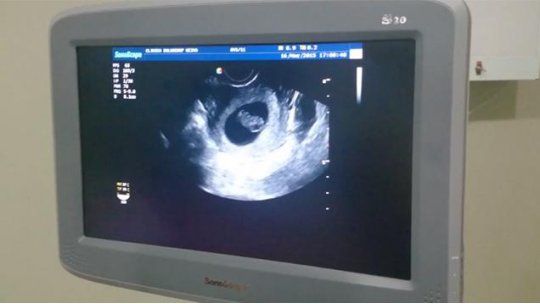

La mujer que por decisión judicial debe seguir adelante con su embarazo, pese a haber iniciado el procedimiento para abortar en una mutualista de Mercedes, Soriano, dijo a Subrayado que tiene una lesión en el útero y que por eso no puede desarrollar un embarazo normal sin estudios previos de alta complejidad y cuidados especiales.

Sostiene que por eso no puede desarrollar un embarazo normal sin estudios previos y cuidados especiales. Presenta documentación.

Contó que esa lesión se presentó ya en su primer embarazo (su hijo tiene ahora cinco años) y que entonces estuvo varios meses en quietud y bajo observación médica.